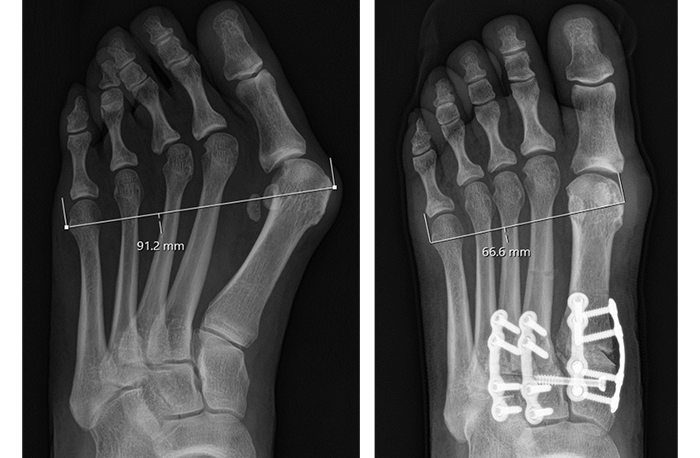

Adductoplasty® Midfoot Deformity Correction Before & After Results

Scroll through case examples to see the results

Individual results may vary. These experiences are specific to these patients only.